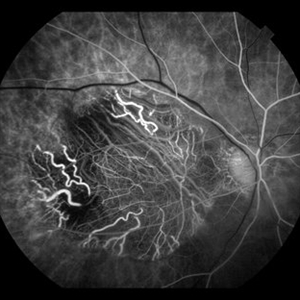

Sickle Cell Retinopathy with Sea Fans (angiography)

Fluorescein angiography (early/mid phase) of a 40-year-old man with African heritage and sickle SC disease. Sea fans are present temporal to the macula (leaking fluorescein).

Photographer: Geoffrey G. Emerson, MD, PhD, Retina Center, Minneapolis

Condition/keywords: sea fan, sickle cell retinopathy